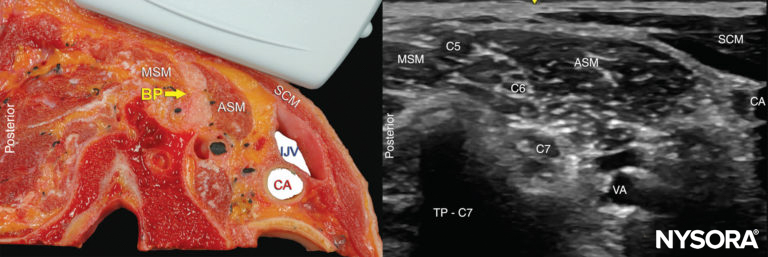

The brachial plexus at the interscalene level is seen lateral to the carotid artery and internal jugular vein, between the anterior and middle scalene muscles (Figures 1 and 2).

FIGURE 1. Anatomic relationships of the brachial plexus at the interscalene level

FIGURE 2. Cross-section anatomy for interscalene brachial nerve block and transducer position to obtain the desired views. The plexus (BP) is seen between the middle scalene muscle (MSM) laterally and anterior scalene muscle (ASM) medially. The ultrasound image includes a partial view of the lateral border of the sternocleidomastoid muscle (SCM) the internal jugular vein (IJV), carotid artery (CA) and the transverse process of C7 (TP-C7).

The prevertebral fascia, superficial cervical plexus, and sternocleidomastoid muscle are seen superficial to the plexus. The transducer is moved in the proximal-distal direction until two or more of the brachial plexus elements are seen in the space between the scalene muscles. Depending on the depth of field selected and the level at which scanning is performed, the first rib and/or the apex of the lung may be seen. The brachial plexus is typically visualized at a depth of 1–3 cm.